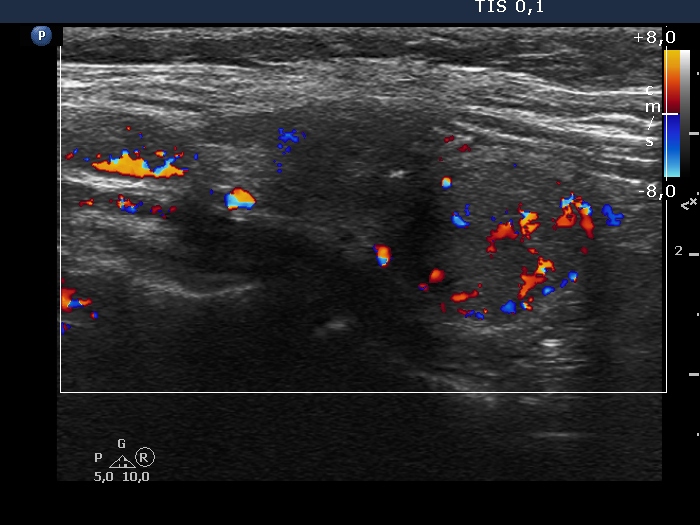

Lower pole of the right lobe, longitudinal scan. This nodule has intranodular vascularization.